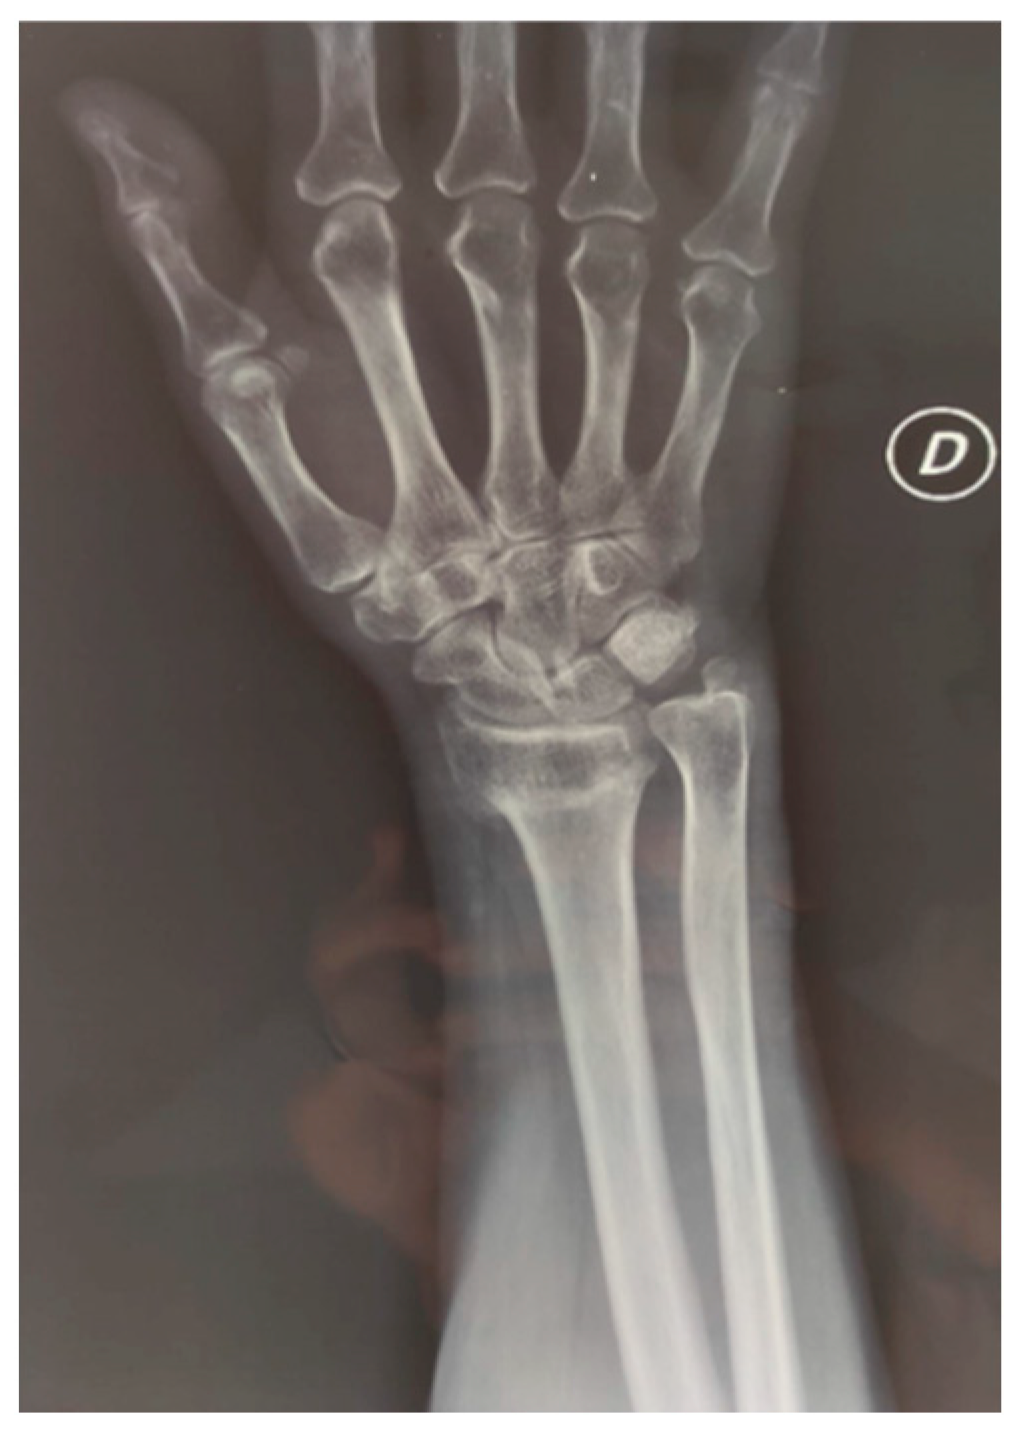

3.1. Findings in Distal Radial Fractures

- Rehabilitation intervention versus no intervention (started during the treatment period) (Figure 3.1).

- Rehabilitation intervention versus no intervention (started post-immobilisation) (Figure 3.1).